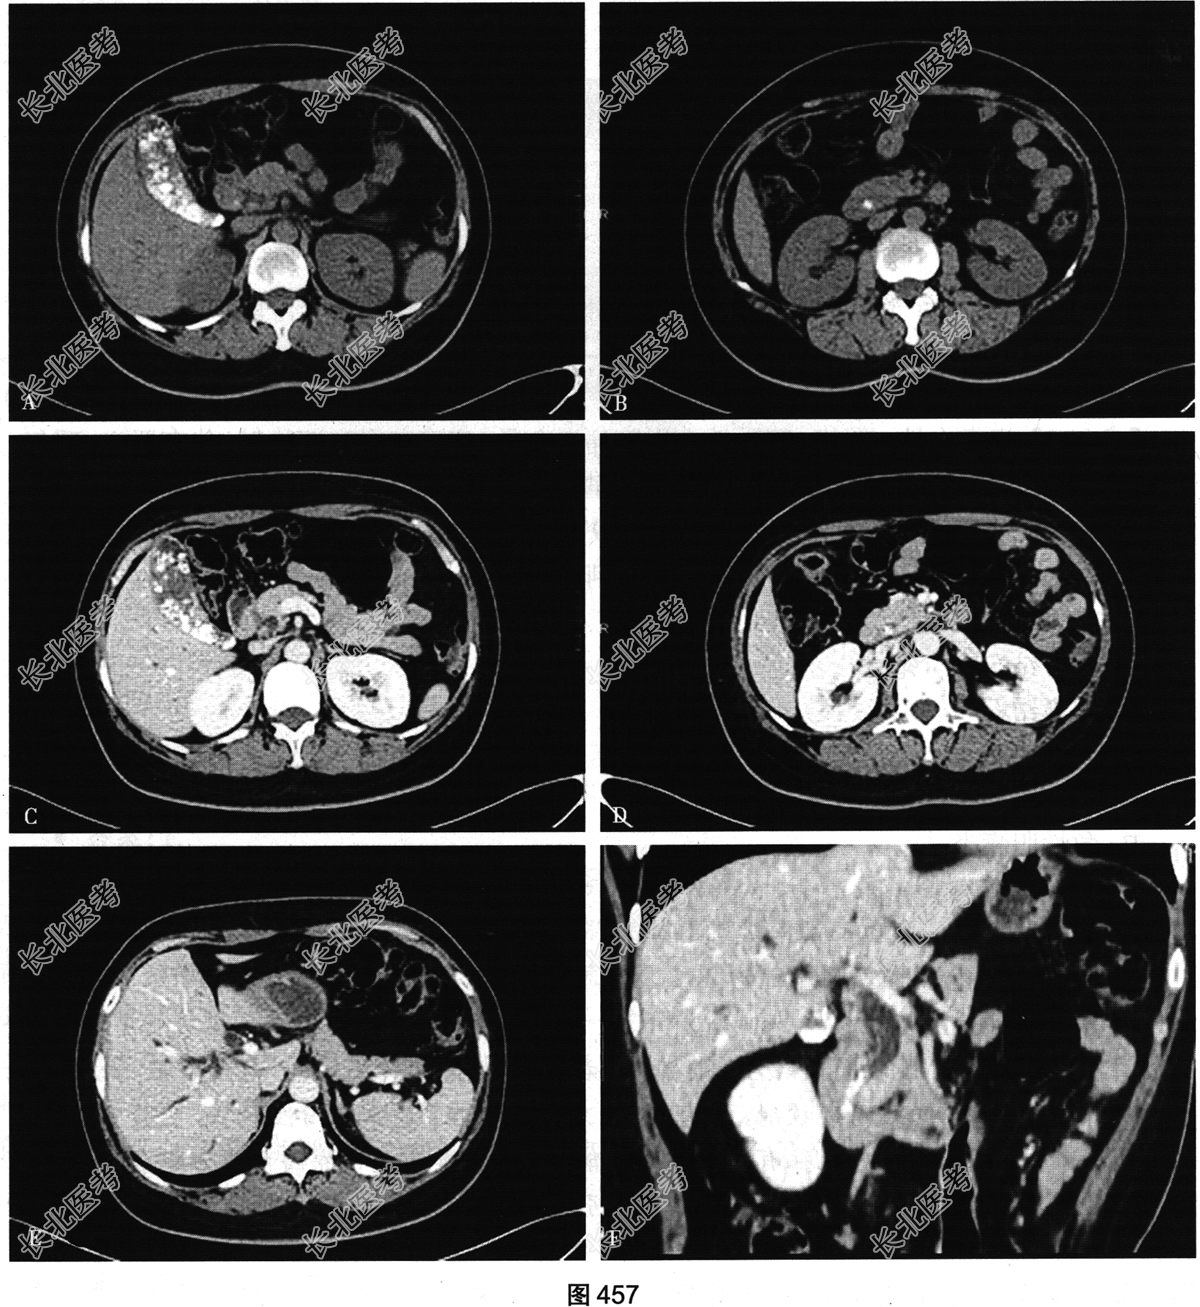

- 多项选择题3.[提示]患者急诊行CT检查,如图457所示。根据CT图像, 患者可能的诊断是( )

A、胃肠道穿孔

B、腹膜炎

C、肝内胆管结石

D、急性胰腺炎

E、肾结石

F、输尿管结石

G、胆囊炎

H、胆总管结石

I、胆管炎

J、胆囊结石